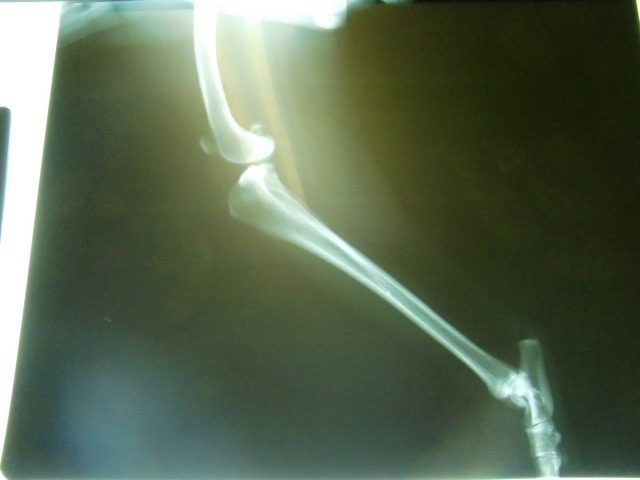

すぐに駆け寄り状態を見るも右後ろ足をかばっていて歩けるような状態ではなくもはや素人には分かる範疇ではなくすぐに病院へ。

触診では「恐らく前十字靱帯損傷で折れてはいないと思うけど分からない」とのことだったのでレントゲンもお願いしたところやはり前十字靱帯断裂が濃厚に。

前十字靭帯断裂

体重11.3kg

再診料 500

レントゲン 5000

薬処方(リマダイル 3T) 1000

---------------------------

合計 ¥6500-